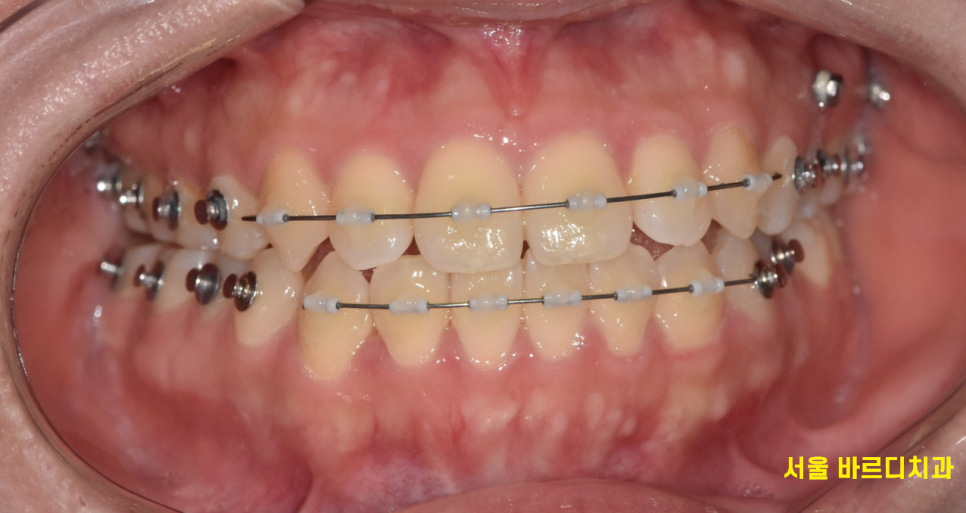

250201 임플란트가 심어져있는데 교정을 진행하는 케이스

교정치료를 결심하기 전 이미 심어둔 임플란트가 있을 수 있는데요~

주로 중년 환자분들이 앞니 삐뚤빼뚤한 것을 개선할 때

이런 경우가 많아요~

250201

이럴 경우 임플란트를 제외하고

나머지 치아들을 최대한 움직여 교정을 진행합니다.